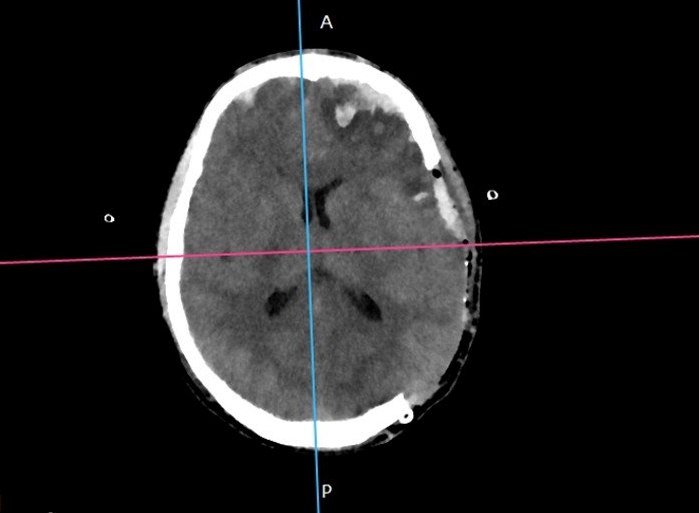

Один из водителей электросамокатов, мужчина 1995 года рождения (30 лет), до сих пор находится в тяжёлом состоянии. Он столкнулся с автомобилем и получил черепно-мозговую травму, потребовавшую трепанации черепа (вскрытия костей черепа) и удаления гематомы. Кровь скопилась в черепной коробке. Часть мозга вышло за пределы черепа.

череп.jpg

После лечения потребуется ещё длительная реабилитация, рассказал заведующий отделением нейрохирургии Антон Волков.